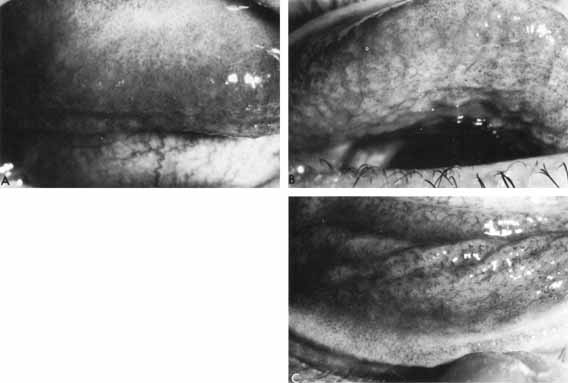

The corneal stroma is the site of an inflammatory reaction that is irregularly distributed, is of varying intensity and is accompanied by an anterior uveitis. Epithelial keratitis, as previously described, is variably present. In addition, there may be a more generalized epithelial edema in which the epithelium may be separated from Bowman's layer by the edema fluid (Fig. 19).The corneal lamellae may be necrotic in places, and inflammatory cells, predominantly polymorphonuclear leukocytes, diffusely and focally infiltrate the stroma. The process may involve the cornea at all levels from Bowman's layer to Descemet's membrane. The endothelium may be edematous or infiltrated by inflammatory cells and, especially beneath the stromal lesion, may be replaced by a coagulated film of fibrin and inflammatory cells. Keratic precipitates are prominent. The aqueous contains fibrin and inflammatory cells (neutrophils, lymphocytes, macrophages, and plasma cells). These cells frequently infiltrate the angle and the trabecular bands are thickened and appear edematous, so the term trabeculitis appears justified. Involvement of the iris is variable, but it is frequently infiltrated by lymphocytes and plasma cells and thickened by edema. The anterior ciliary body shows a similar involvement. Posterior synechiae and anterior lens changes are common, frequently in association with a fibrovascular membrane extending across the pupil.

Fig. 19 Gross epithelial edema with bullae, resulting from severe endothelial decompensation, in an eye that had previously been the site of a severe herpetic uveitis. As edema resolved, endothelium was seen to be studded with numerous secondary guttatae.

When the stroma is edematous, it exhibits a ground-glass appearance and is thickened. Edema commonly encompasses the infiltrate and, at times, is the main feature of the disease and it is also an essential component of the stromal inflammatory reaction. It may result in endothelial dysfunction secondary to uveitis.

In the epithelium, a fine superficial edema, occupying a variable surface area over the active stromal lesion, is common and is related to endothelial dysfunction. At times the epithelium is grossly edematous, with recurrent bullae appearing and sometimes breaking down to form indolent ulcers that have to be distinguished from active epithelial viral disease. Punctate erosions that stain well with rose bengal and fluorescein are frequently seen.

The endothelial layer of the cornea is involved in all but the most superficial lesions. Fine, white keratic precipitates may be scattered over the surface or crops of discrete white precipitate may appear (Fig. 24). Some of these lesions become pigmented. It is not unusual for large endothelial plaques to develop in relation to the active stromal lesion (Fig. 25). Secondary guttae are quite common but usually reversible.

Fig. 24 Typical keratic precipitates in an eye with a disciform keratitis caused by herpes.

Fig. 25 Large endothelial plaque behind disciform keratitis.